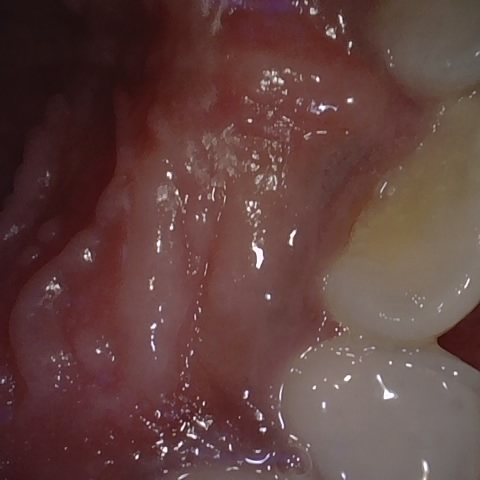

Annotated as "Good"